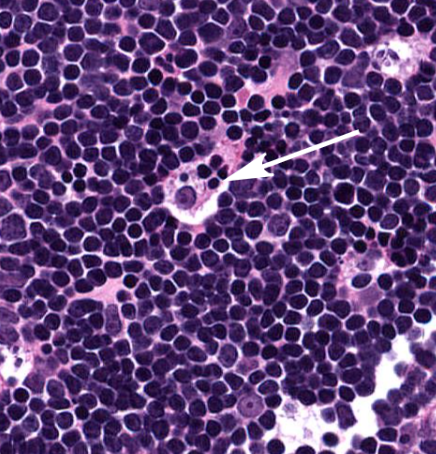

thymus

LARGE tightly packed lymphocytes

macrophage (shown in the thymus)